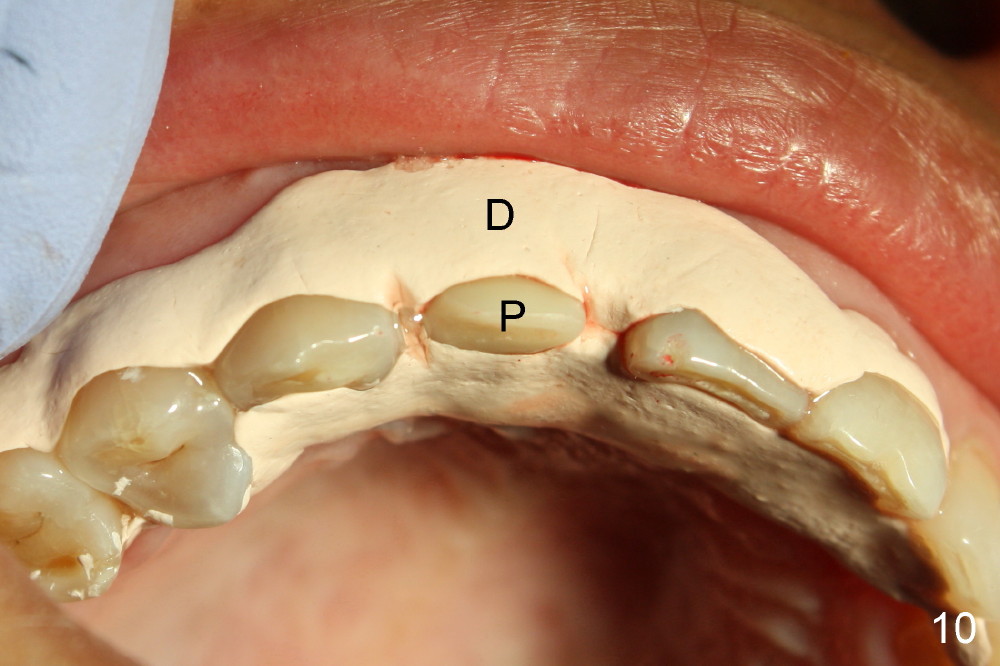

Malpositioned implant in the anterior region is cosmetically unacceptable. Immediate provisional allows us to note the issue immediately. The crown looks too long. Secondly, the provisional is easily dislodged, since the buccal aspect of the angled abutment is over trimmed (Fig.1). The implant (3.8x14 mm), which has been placed 3.5 months, is unexpectedly easily removed by reverse torque (Fig.2). The buccal wall is intact, whereas there seems to be enough bone lingually to place an implant. A small incision is made (Fig.11) so that the gingival tissue can be transferred buccally (Fig.12) and the immediate implant is to be placed palatally (Fig.13 white circle). There is no difficulty forming osteotomy in the palatal wall, followed by inserting 4.5x20 mm tap at the depth of 17 mm (Fig.3,5). But the tap is not palatal enough (Fig.4). By removing more palatal bone, the 4.5x17 implant (Fig.6) appears to be placed palatally enough for restoration (Fig.7; A: abutment; *: buccal gap). The biggest problem is that the palatal flap (Fig.7 arrowheads) cannot be pushed buccally; instead remains palatally. This leads to buccal tissue deficiency (Fig.8). Connective tissue graft is offered, but declined. The patient insists that she has low smile line. Following immediate provisional, mixture of allograft and synthetic graft is placed in the buccal gap (Fig.9). The overbuilt graft is held in place by perio dressing.